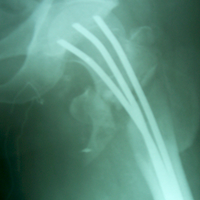

Case:9 Comminuted Intertrochanteric Fracture

Patient aged 75 years with Comminuted Intertrochanteric fracture treated with closed reduction & Ender’s nailing.

Pre-op Ap

Pre-op Lateral

Post-op Ap

Post-op Lateral